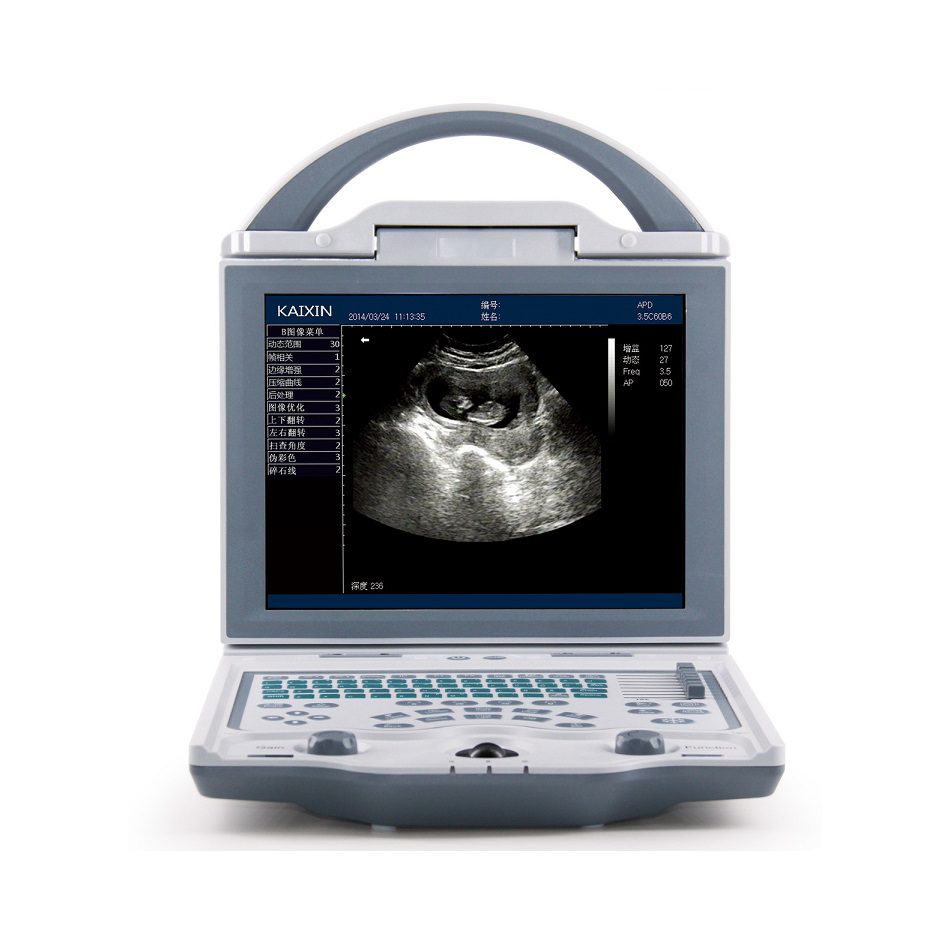

Rechargeable Human Ultrasound Scanner -KX5600

KX-5600 Full Digital B Mode Ultrasound Machine

1.Humanized design

2.Rapidly one-key operation includes one-key storage, one-key browse and one-key print

3.Unique CPU temperature control function, when the temperature is too high, it can automatically shut down.

4.Rotatable LED Panel to make the users get the best image visual sense from different angles.

5.One-key to light the keyboard, suitable for operation dark room

6.Practical function knob design,use A key to realize quick adjustment in a variety of conditions.

7.Powerful data management system

8.Optimization of the query image function, can realize 1-2 seconds to your needs.

9.internal work station multi-plan template,quickly finish data manage function, realize process multi medical histories function

10.Abundant software package

11.Equipped with professional gravel package which can realize real time positioning measurement.

12.OB measurement and analysis 1s kinds OB table and several GA measurement AFI, Fetus growth curve and OB report

13.GYN measurement and analysis general GYN software packages and GYN report

14.Urological measurement and analysis residual urine, volume of prostate,Urological report.

15.High quality clinical image

16.A High resolution and full screen display ,meet your vision needs

17.Adjustable LED brightness, convenient and practical